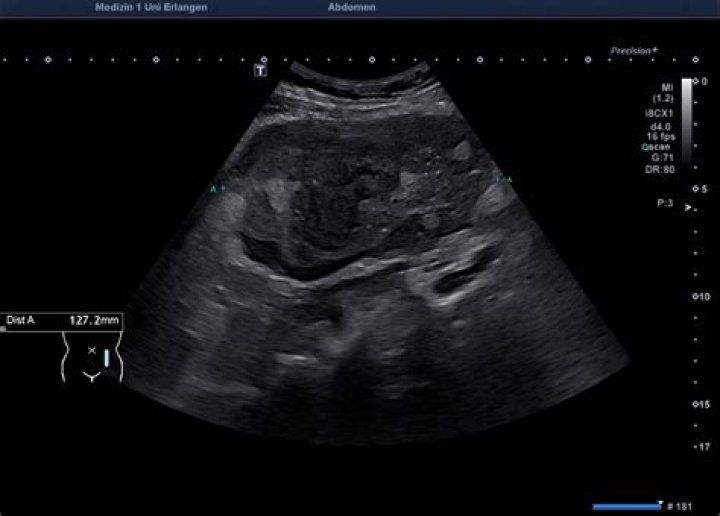

Do lymphoma lymph nodes look different on ultrasound?

Lymph nodes in lymphomas may be indistinguishable from reactive lymph nodes in ultrasound, also with the application of color or power Doppler option (Fig. 4) (3, 4).

What do lymphoma lymph nodes look like on ultrasound?

On grey scale ultrasound, lymphomatous nodes tend to be round in shape, well-defined, appear hypoechoic and are usually without an echogenic hilus29,,,, features which are similar to most metastatic lymph nodes.

What does an abnormal lymph node look like on ultrasound?

Sonographic features that help to identify abnormal nodes include shape (round), absent hilus, intranodal necrosis, reticulation, calcification, matting, soft-tissue edema, and peripheral vascularity. Metastatic cervical lymph nodes are common in patients with head and neck [1] and non–head and neck [2] cancers.